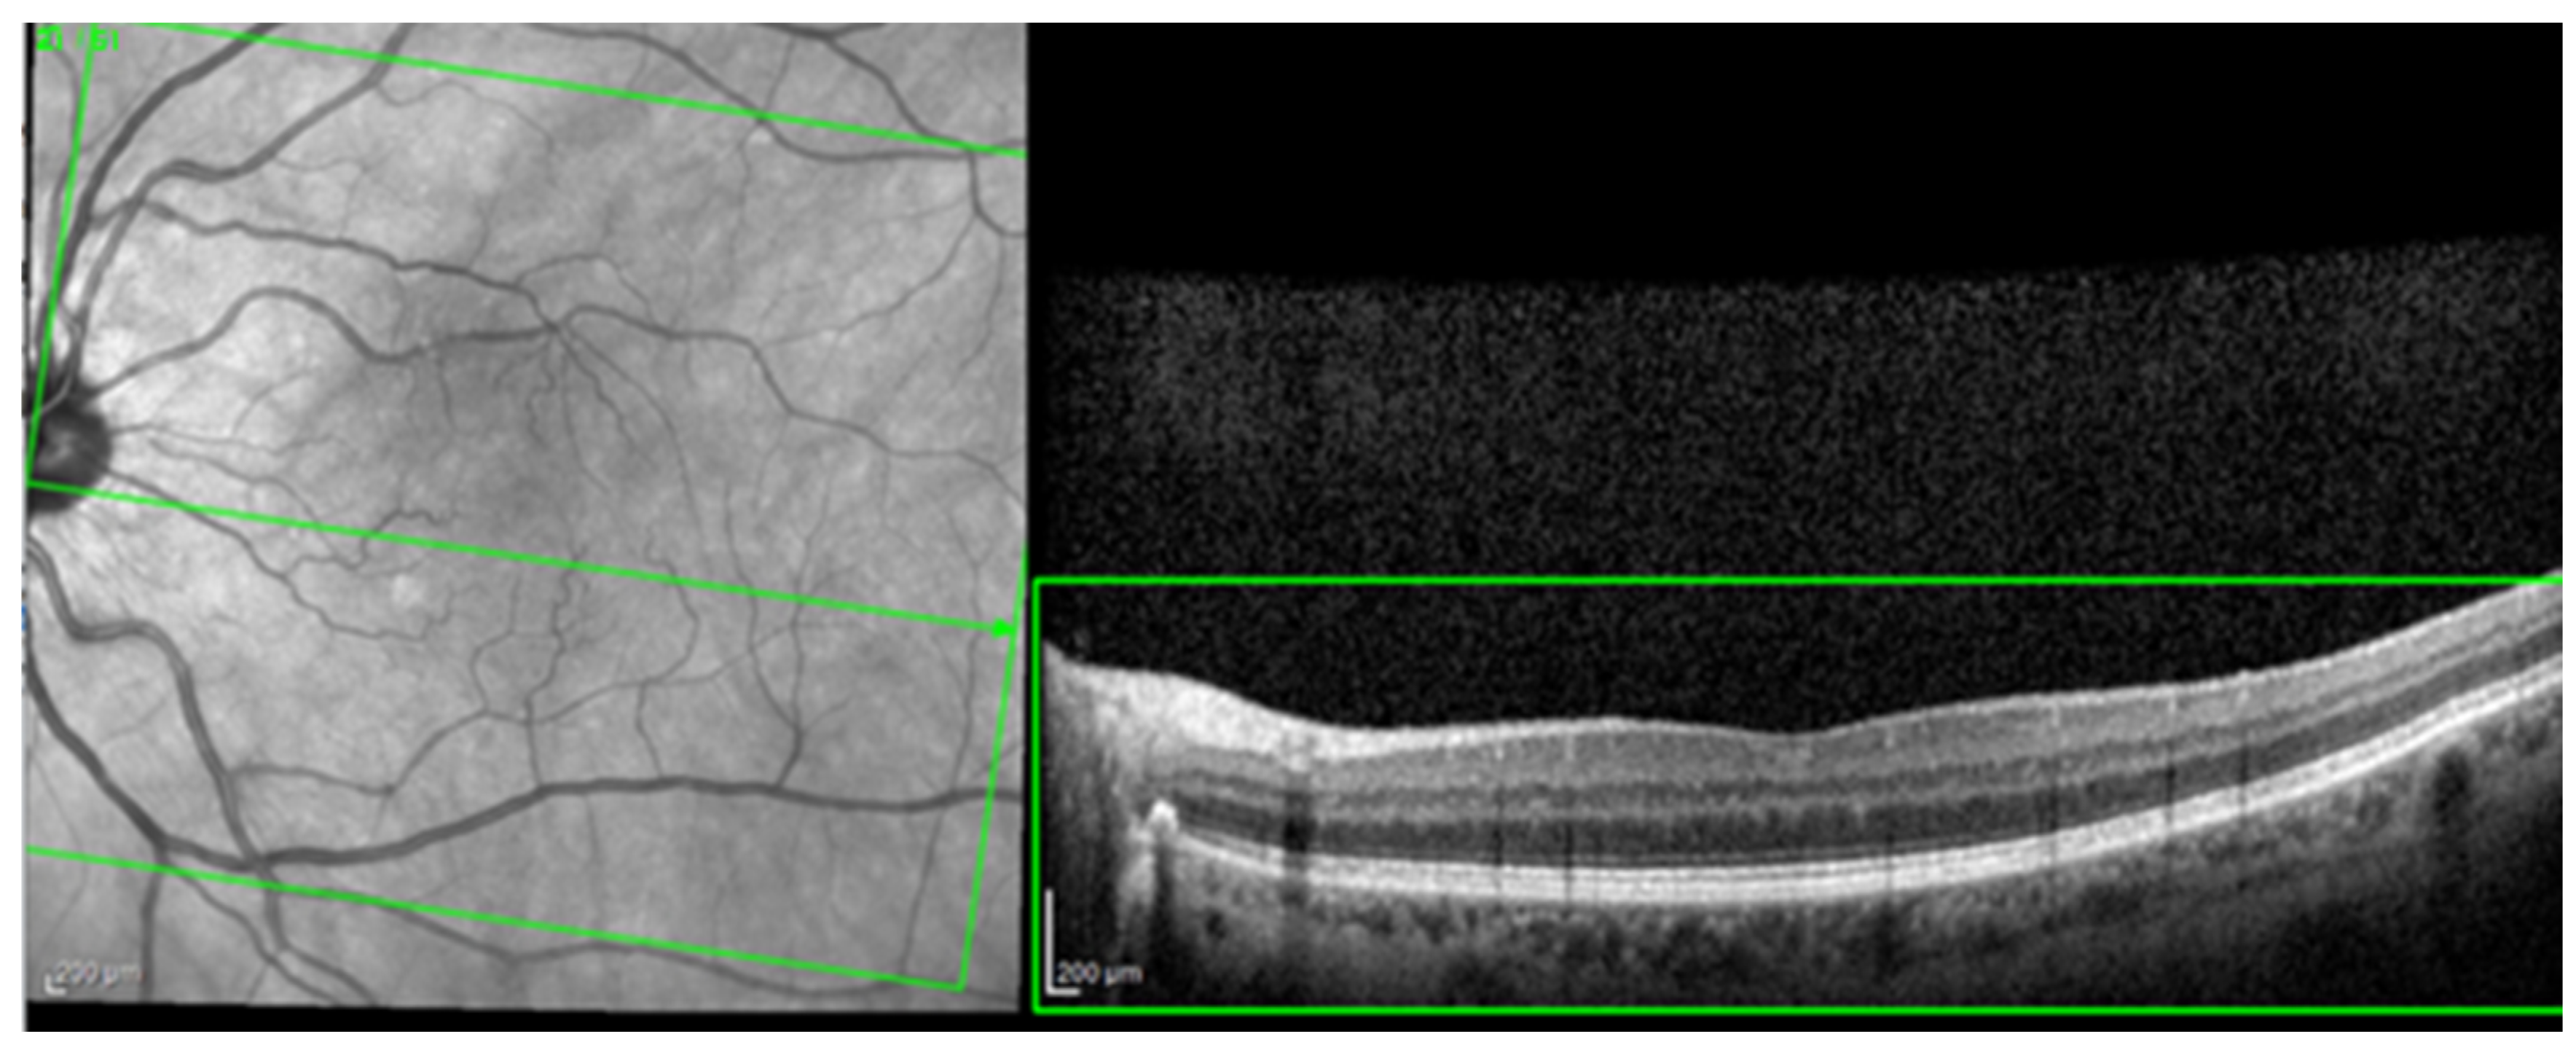

The Heidelberg Engineering Spectralis Spectral Domain-OCT device with the EyeTracking feature enabled (Heidelberg Engineering GmbH, Heidelberg, Germany) was used to examine all the enrolled subjects, and was performed with Heidelberg Spectralis® OCT2 Module Infrared Reflectance (Spectralis Software version 6.10.5) with fast macular scan and thickness map rendering using 20 × 20° scan with 25 slices/retina at 200 µm and an automatic, real-time value of 9. The ETDRS map was rendered by the device software and used for clinical analysis.

For the AI interface input, from the original OCT image acquisitions, a region of interest (ROI) was cut and standardized at a resolution of 256 × 256 pixels in order to have comparable input data for the software algorithm (see Figure 1).

Figure 1.

The selection of a region of interest (ROI) from an original optical coherence tomography (OCT) image (green box).

The most common image artifacts observed were distortions and image noise. All images were included in the analysis, without having any external image adjustments or quality enhancers, in order to emulate “real world” everyday clinical practice conditions (see Figure 2 and Figure 3).

Image distortion. Observe the rhomboid aspect of the image slice (green box) giving the sense of a scan from an angle rather than a perpendicular scan to the retina’s base. This artifact is probably due to a sudden and rapid movement of the eye during scanning.

Figure 3.

Image noise. Observe the snow-like appearance of the scan (green box). This artifact appears when the medium through which the infrared beams pass are not perfectly transparent (example: cataracts), making it very difficult to interpret the image.